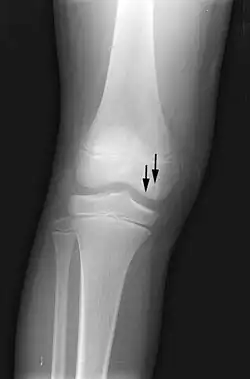

X-ray images of avascular necrosis in the early stages usually appear normal. In later stages it appears relatively more radio-opaque due to the nearby living bone becoming resorbed secondary to reactive hyperemia.[2] The necrotic bone itself does not show increased radiographic opacity, as dead bone cannot undergo bone resorption which is carried out by living osteoclasts.[2] Late radiographic signs also include a radiolucency area following the collapse of subchondral bone (crescent sign) and ringed regions of radiodensity resulting from saponification and calcification of marrow fat following medullary infarcts.

Radiography of total avascular necrosis of right humeral head. Woman of 81 years with diabetes of long evolution.